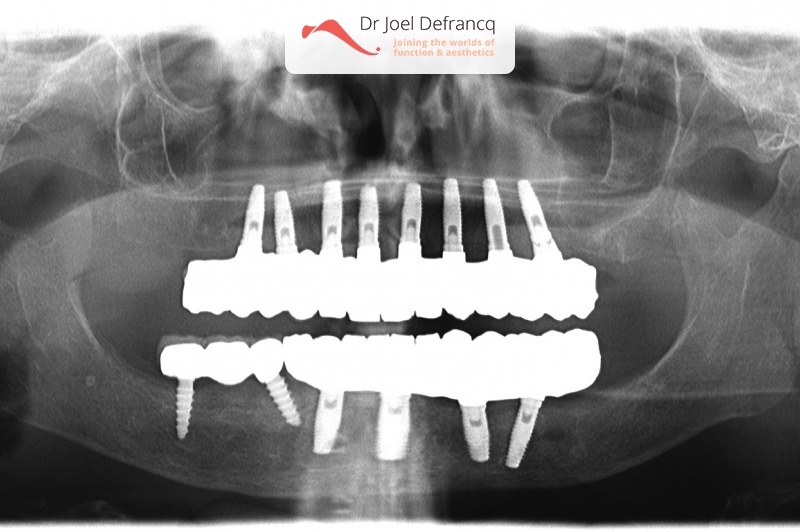

Bashira: all in for concept with immediate loading.

Dentale diagnose

- Klasse I

Behandeling tandheelkundige implantaten

- Vaste tanden op implantaten (bovenkaak)

- Vaste tanden op implantaten (onderkaak)